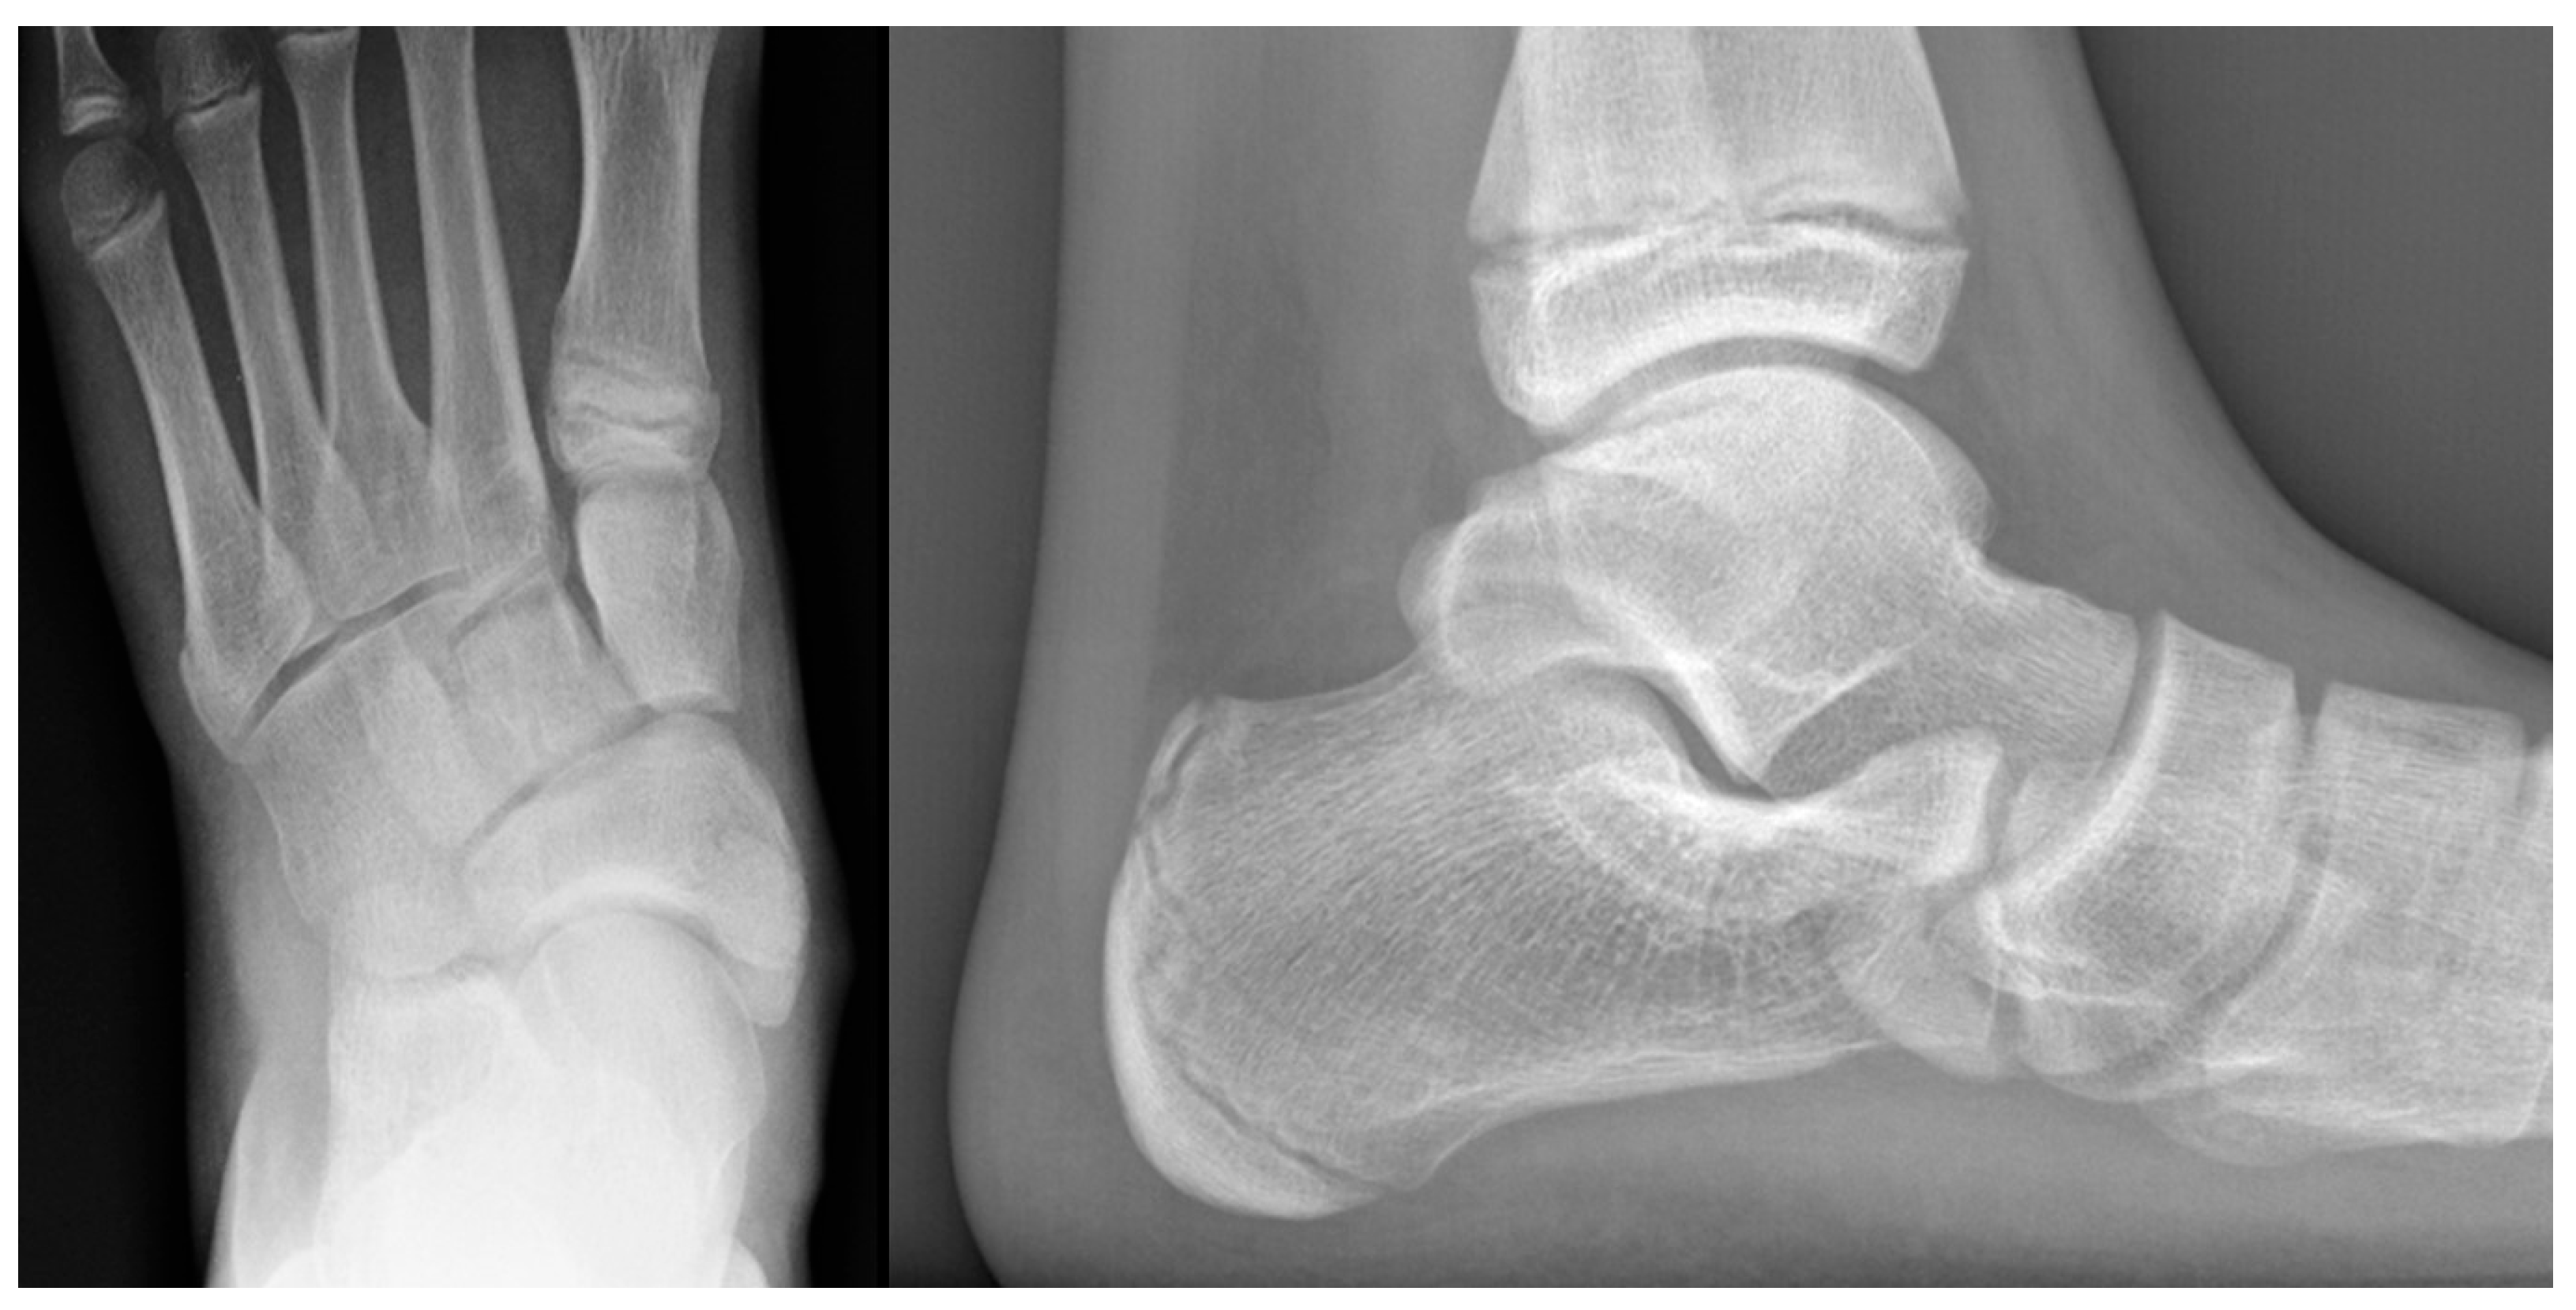

2.7.5. Diagnosis

While the clinical findings can strongly suggest the presence of osteochondrosis, imaging is crucial for confirming the diagnosis and determining the extent of bone involvement.

Plain radiographs are the cornerstone of imaging in the diagnosis of lesser metatarsal osteochondrosis. In the early stages of the disease, when supported by a suggestive clinical presentation, obtaining a comparative radiograph of the contralateral foot can be a useful diagnostic tool (Figure 9).

Figure 9.

Radiograph of a symptomatic 10-year-old female patient showing early sclerosis and flattening of the second metatarsal head on the left foot, compared to the contralateral side.

In the later stages, radiographs may reveal characteristic changes including subchondral sclerosis, fragmentation, and flattening of the affected metatarsal head (Figure 10 and Figure 11). In some cases, the presence of joint space narrowing or bony irregularities may also be observed. However, early changes, such as bone marrow edema or subtle cartilage damage, may not be visible on standard radiographs. MRI is particularly useful in the early stages of the disease, as it can detect bone marrow edema, which is a sign of active bone inflammation and necrosis, even before structural changes become apparent on radiographs (Figure 10, Figure 11 and Figure 12).